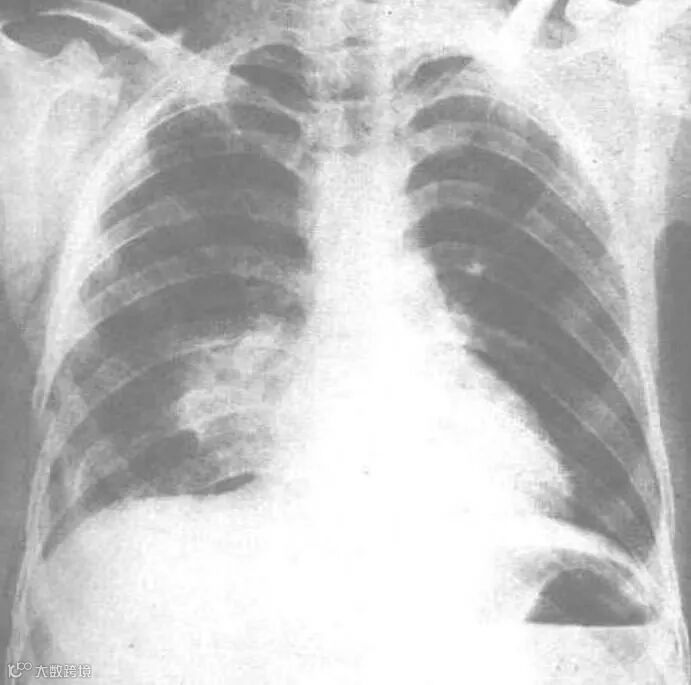

Z先生的父亲被诊断为肺挫伤、颅骨骨折、膝关节处闭合性损伤,且治疗时间较短,预计两三天病情可能会加重。医疗团队与其主治医生均建议采取保守治疗,以观察为主。远盟力码救援第一时间将父亲的诊疗情况告知Z先生。yua

本文转载自公众号「远盟救援」,引用图片与内容无关,另为保障患者及家属隐私,以上案例涉及的患者及家属姓名及其他信息均做虚构处理。

图片:网络